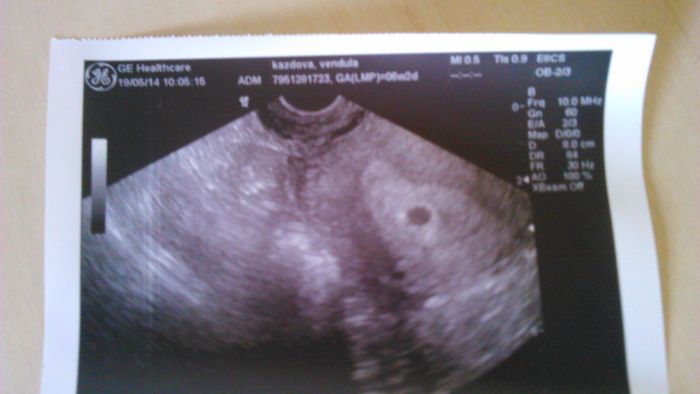

Jinak tomu malému teď říkáme "Delfínek" přikládám fotečku s prvního ultrazvuku :-)

[591174] no tak to je uuuuzasna fotecka jasny delfinek :)